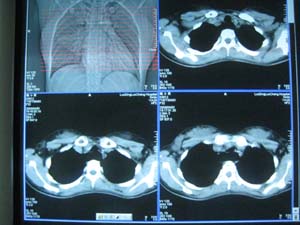

以下是引用卜一在2009-4-1 22:24:00的发言:[br][br] [br] 右肺中叶不张合并感染,建议支气管镜检查排除ca。不能看年轻就不考虑ca,肺ca 也年轻化了。非常支持!. [br] [br]

以下是引用当兵的在2009-4-1 23:13:00的发言:[br]右肺中叶不张合并感染,建议支气管镜检查。[br]食管呈大萝卜根,贲门失迟缓,